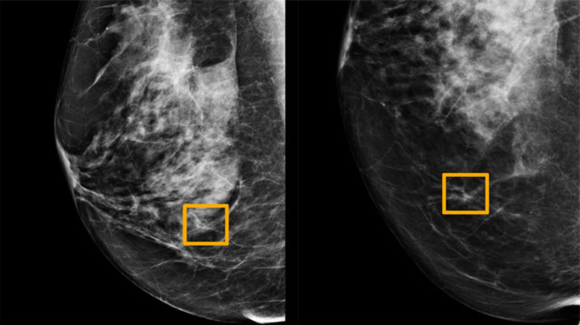

국내 첫 의료AI 스타트업으로 지난 2013년 설립된 루닛은 이달 1일 노벨 생리의학상 수상자를 선정하는 스웨덴 왕립 카롤린스카연구소가 진행한 유방암 진단 AI 비교 연구에서 최고 평가를 받았다. 유방암을 정확하게 찾아내는 민감도 지표가 81.9%로 의사들의 77.4%보다 높은 것으로 분석됐다. 또 다른 국내 스타트업인 뷰노는 흉부 엑스레이 영상 판독 AI가 서울아산병원 건강증진센터에서 활용되기 시작, 인공지능 AI와 전문의가 함께 진단을 결합하면 정확도는 더 높아진다

유방암 검진을 위한 구글의 인공지능(AI) 모델을 의료 이미징 시스템에 통합하기 위해 의료 기술 회사인 아이캐드(iCAD)와 구글이 계약을 체결했다. 이는 구글의 유방조영술 AI 모델에 대한 첫 라이선스 및 상용화 계약이어서 주목된다. 구글은 이 기술을 실제 임상에 적용할 예정이며 아이캐드의 기술은 미국 전역과 전 세계 7500여 개의 의료 시스템 및 이미징 센터에서 사용된다. 구글의 유방 조영술 AI 연구 모델을 아이캐드의 기존 도구에 통합할 계획으로 첫 번째는 3D 유방 조영술이라고도 하는 고급 이미징 기술인 DBT(디지털 유방 합성법)의 이미지를 분석하는 프로 파운드 AI(ProFound AI) 도구다

이 도구는 악성 연조직 밀도 및 석회화를 찾기 위해 DBT 이미지를 스캔한다. 아이캐드는 또한 위험 평가 도구에도 구글의 모델을 사용한다. 구글은 2018년에 영국 및 미국의 임상 연구 파트너와 협력하여 유방암 진단을 개선하기 위한 AI 모델을 테스트하기 시작했고 이 2020년 네이처 저널에 자사의 AI 모델이 유방암 징후를 식별하는 데에서 방사선 전문의를 능가한다는 논문을 발표한 바 있다. 이 논문은 위양성(false positive)을 최대 5.7%, 위음성(false negative)을 최대 9.4%까지 줄일 수 있었다는 초기 연구 결과를 공유했다.